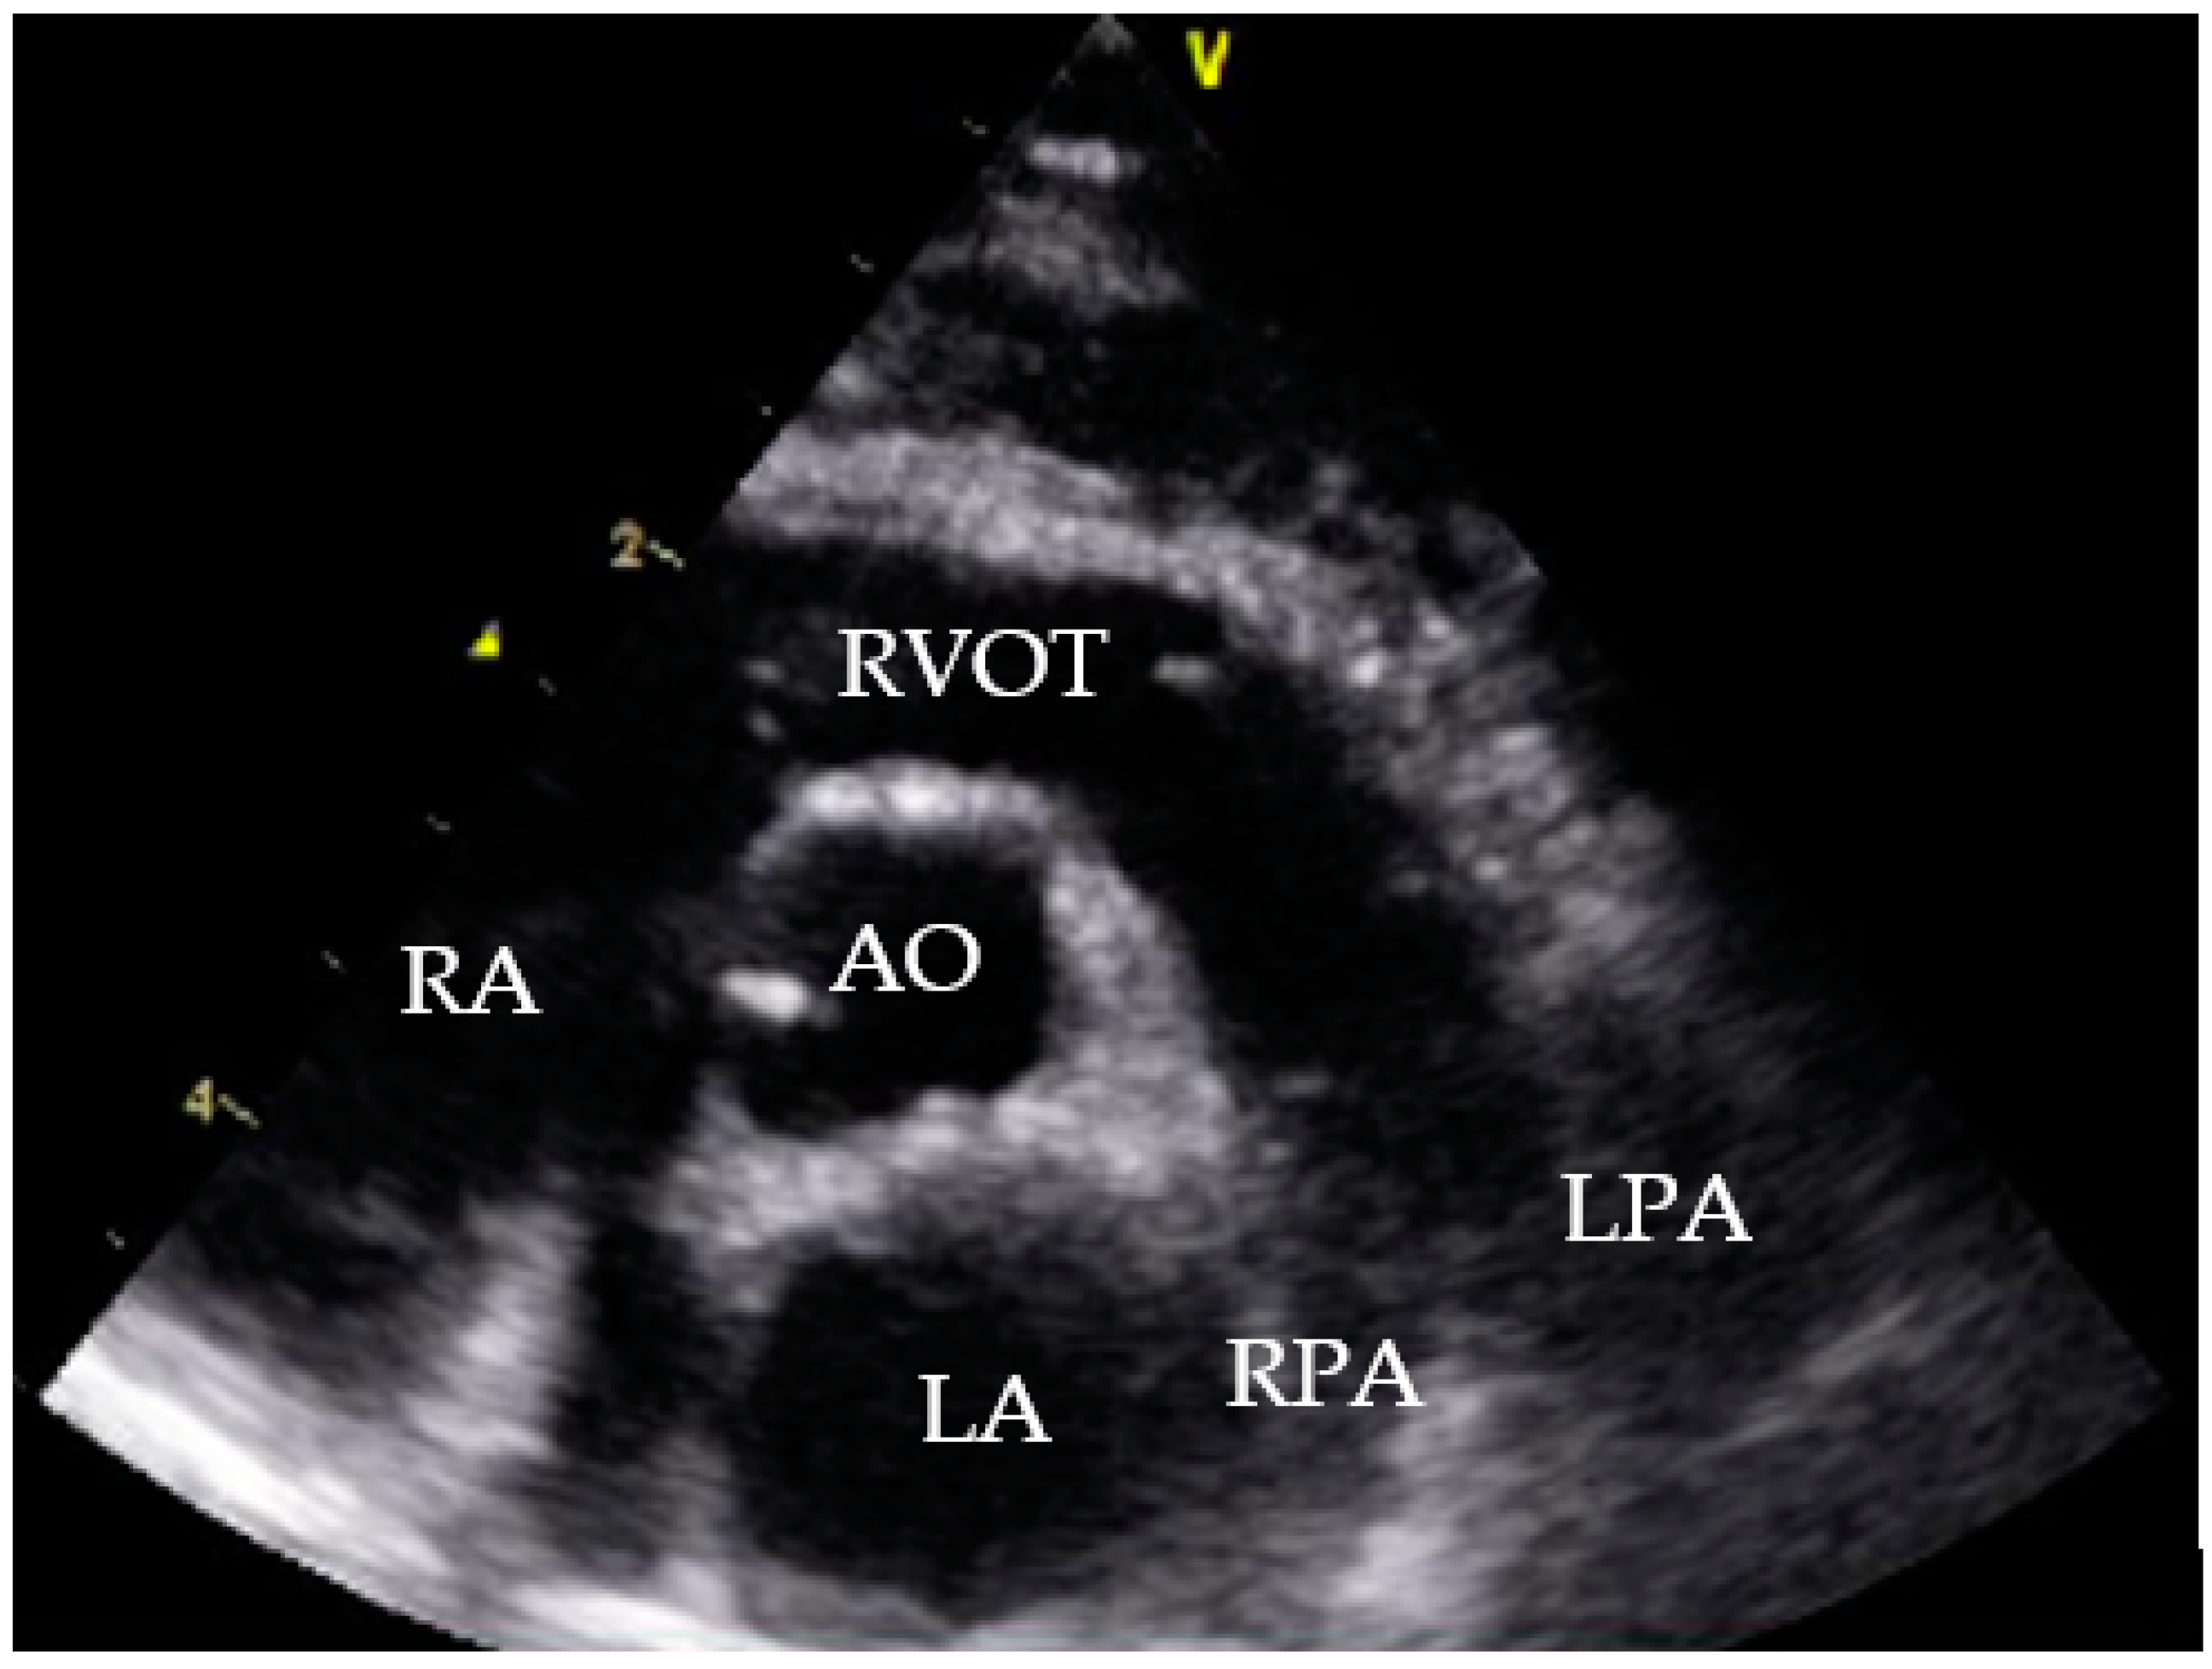

Additionally, an echocardiography was performed. The cat showed a tricuspid insufficiency (2.8 m/s), a mild mitral insufficiency and a pulmonary artery flow of Vmax 1.1 m/s (probably suggesting mild pulmonary hypertension). Comparing the two echocardiograms the cat’s hemodynamic status significantly improved (Table 2) with increased left ventricle preload. No heartworm was detectable (Figure 8). LA/Ao could not be measured in the initial echocardiography due to the enlarged right atrium.

Figure 8. Echocardiogram July 2021, right parasternal short axis view. RA = right atrium; RVOT = right ventricle outflow tract; AO = aorta; LA = left atrium; RPA = right pulmonary artery, LPA = left pulmonic artery.